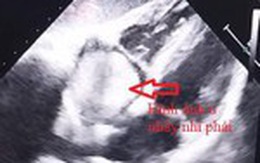

Rất nhiều trường hợp đột tử đáng tiếc do không biết mình có bệnh lý ở tim. Nhiều người rất chăm đi khám sức khỏe định kỳ mà bỏ qua siêu âm tim vì không thấy có biểu hiện bệnh lý ở tim. Họ không biết rằng, rất nhiều bệnh tim,, trong đó có u nhầy không có biểu hiện hoặc khi có biểu hiện thì bệnh đã ở giai đoạn nặng.